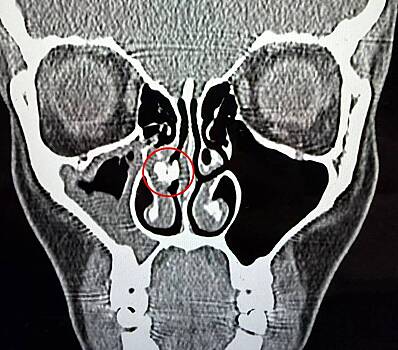

Все изменилось в 2025 году, когда Рейбо обратилась в больницу с синуситом — воспалением слизистой оболочки придаточных пазух носа. Врачи сделали ей компьютерную томографию и обнаружили внутри одной ее ноздри инородное тело неизвестного происхождения.

Спустя час его удалось вытащить из носа пинцетом. Инородное тело оказалось куском скотча. Рейбо показала его в TikTok. Женщина призналась, что не знает, как клейкая лента попала ей в нос и как давно это было.